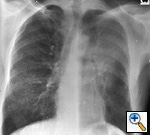

Fig. 8: Posterior-anterior radiograph shows a 6.5 cm left lower lobe bronchogenic carcinoma, T2, without hilar or mediastinal nodal metastases.